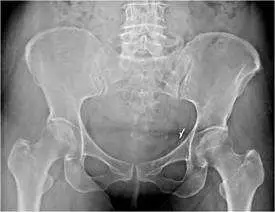

58 歲女性已切除子宮及卵巢,另患有骨盆腔惡性肉瘤,並接受手術及放射治療,主訴最近下背痛, X光及核醫骨掃描如附圖,最可能的診斷為何?

從骨盆平面X光可見雙側sacral alae出現線狀硬化帶,骨質脊緣整齊,未見破壞性病灶或明顯溶骨現象,硬化線平行於sacroiliac joints,符合疲勞性或虛弱性骨折的影像特徵 (ajnr.org)。